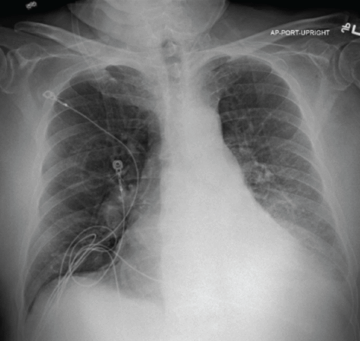

76 y/o male with homogenous emphysema and multiple comorbidities came off oxygen after treatment (Result not typical)

Successful atelectasis of the right middle lobe with 80% fissure completeness score